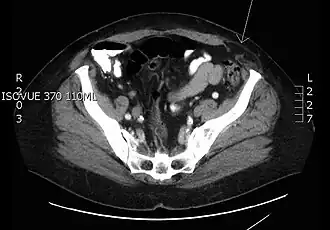

Hernia spiegeli op de plaats van de pijl. | ||||

Een Hernia van Spiegel, ook wel hernia spiegeli of laterale ventrale hernia genoemd, is een hernia door spiegelse fascie. Deze fascie is de aponeurose (het peesblad) tussen de musculus rectus abdominis (de rechte buikspier) mediaal en de linea semilunaris (zie afbeelding) lateraal. Deze hernia's ontwikkelen zich meestal onder de linea semicircularis (de onderrand van de dorsale zijde van de rectusschede) omdat daar het weefsel minder steun heeft. Een hernia spiegeli ontwikkelt zich meestal niet tot aan het subcutane vet, maar blijft pariëtaal, dat wil zeggen tussen de spieren. Hierdoor is de hernia aan de buitenkant vaak niet goed zichtbaar. Doordat de breukpoort vaak klein is heeft deze hernia een grote kans in te klemmen met strangulatie, verstoring van de bloedtoevoer naar de breukinhoud, tot gevolg.

Patiënten presenteren zich gewoonlijk met wisselende zwelling ter plaatse, pijn lokaal of tekenen van darmobstructie.[1] Met echografie of een CT-scan kan de diagnose worden bevestigd.